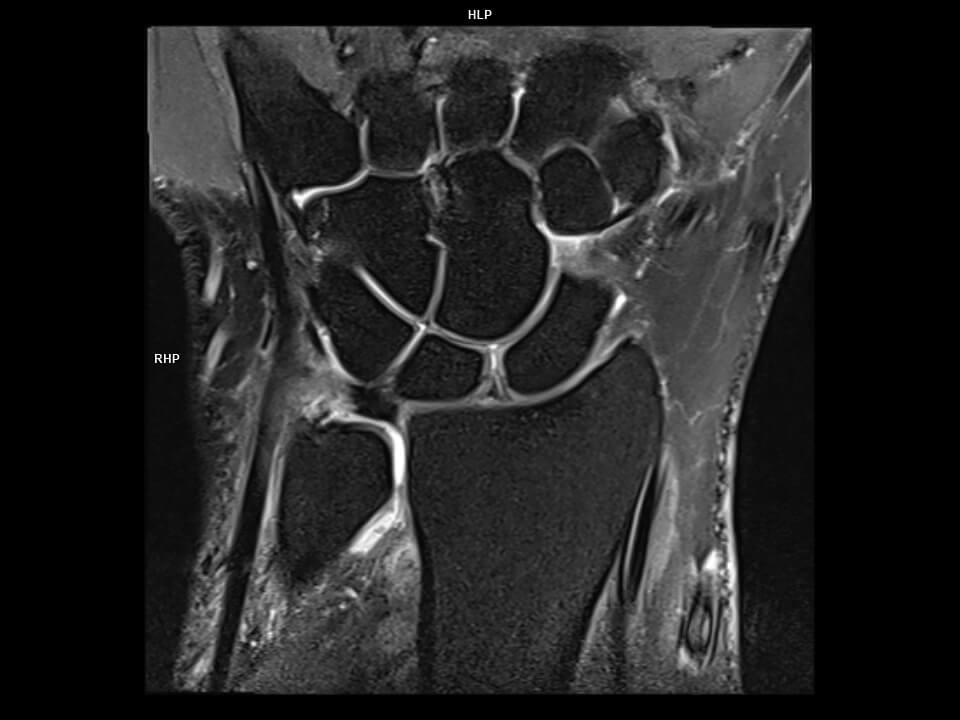

CORONAL PD FS TSE-MAGNETOM Vida

CORONAL PD FS TSE-MAGNETOM Vida/Coil-HAND/WRIST 16/Resolution-384/Scan Time-3:52/Aceleration-p2